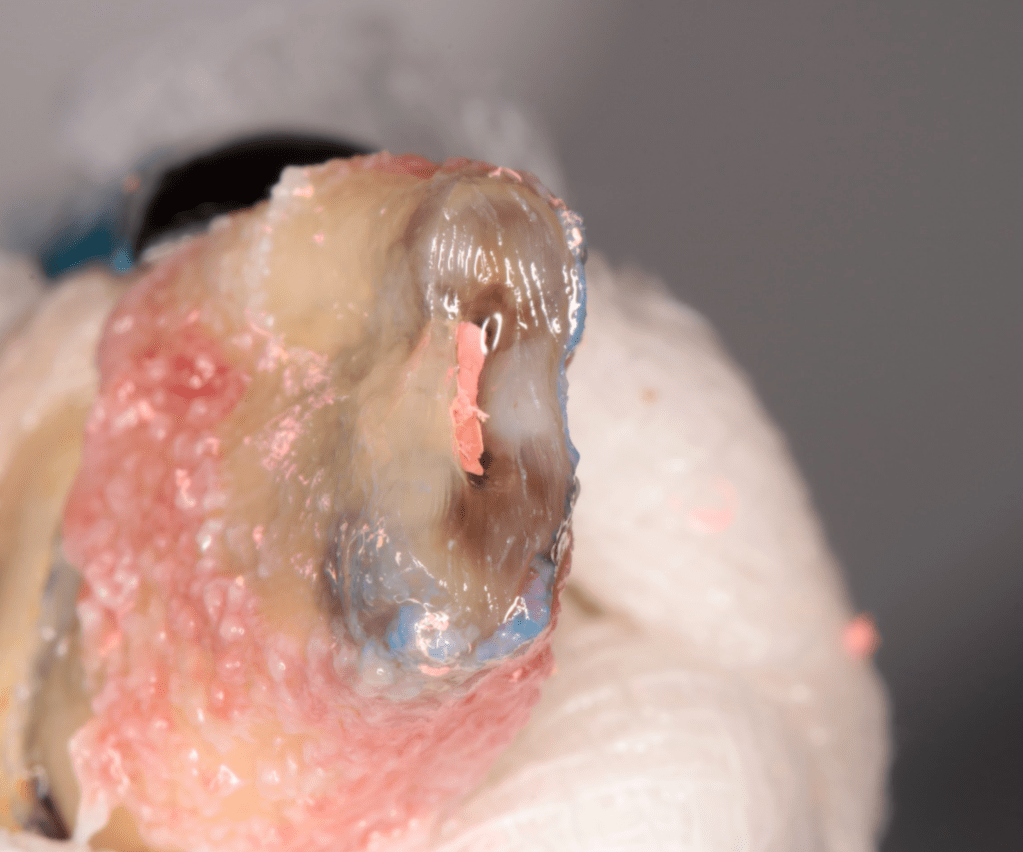

Reconstrucción preendodóntica

Reco pared vesticular